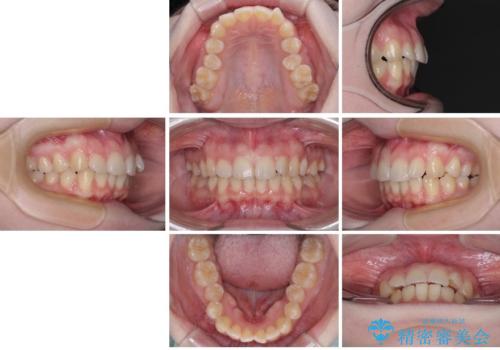

左上の前歯が出ているのが気になる 審美装置による非抜歯ワイヤー矯正

- 左上の前歯が出ていることを主訴として来院された患者様です。

当初はインビザラインを希望されていましたが、職業柄お茶する機会が多く装着時間を確保することが難しいとのことで、相談の上ワイヤー矯正の中では目立ちにくい審美装置で矯正を進めていくこととしました。

1年と少しで矯正治療を終えることができ患者様は大変満足されました。